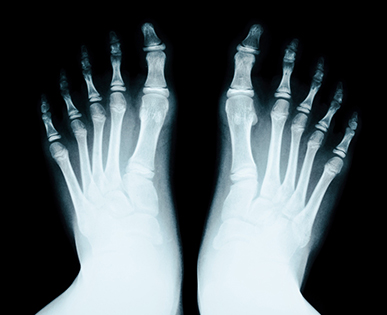

무지외반증

무지외반증은 엄지발가락이 둘째발가락 쪽으로 심하게 휘어져서

엄지발가락 관절이 안쪽으로 돌출된 상태를 말합니다.

발가락이 발등 쪽으로 휘어 올라오거나, 발가락이 축을 중심으로

회전하는 삼차원적인 변형을 뜻합니다.